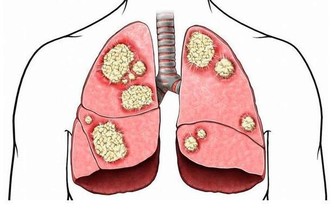

《黃帝內經》講得很清楚:“怒傷肝,喜傷心,悲傷肺,憂思傷脾,驚恐傷腎,百病皆生於氣。”